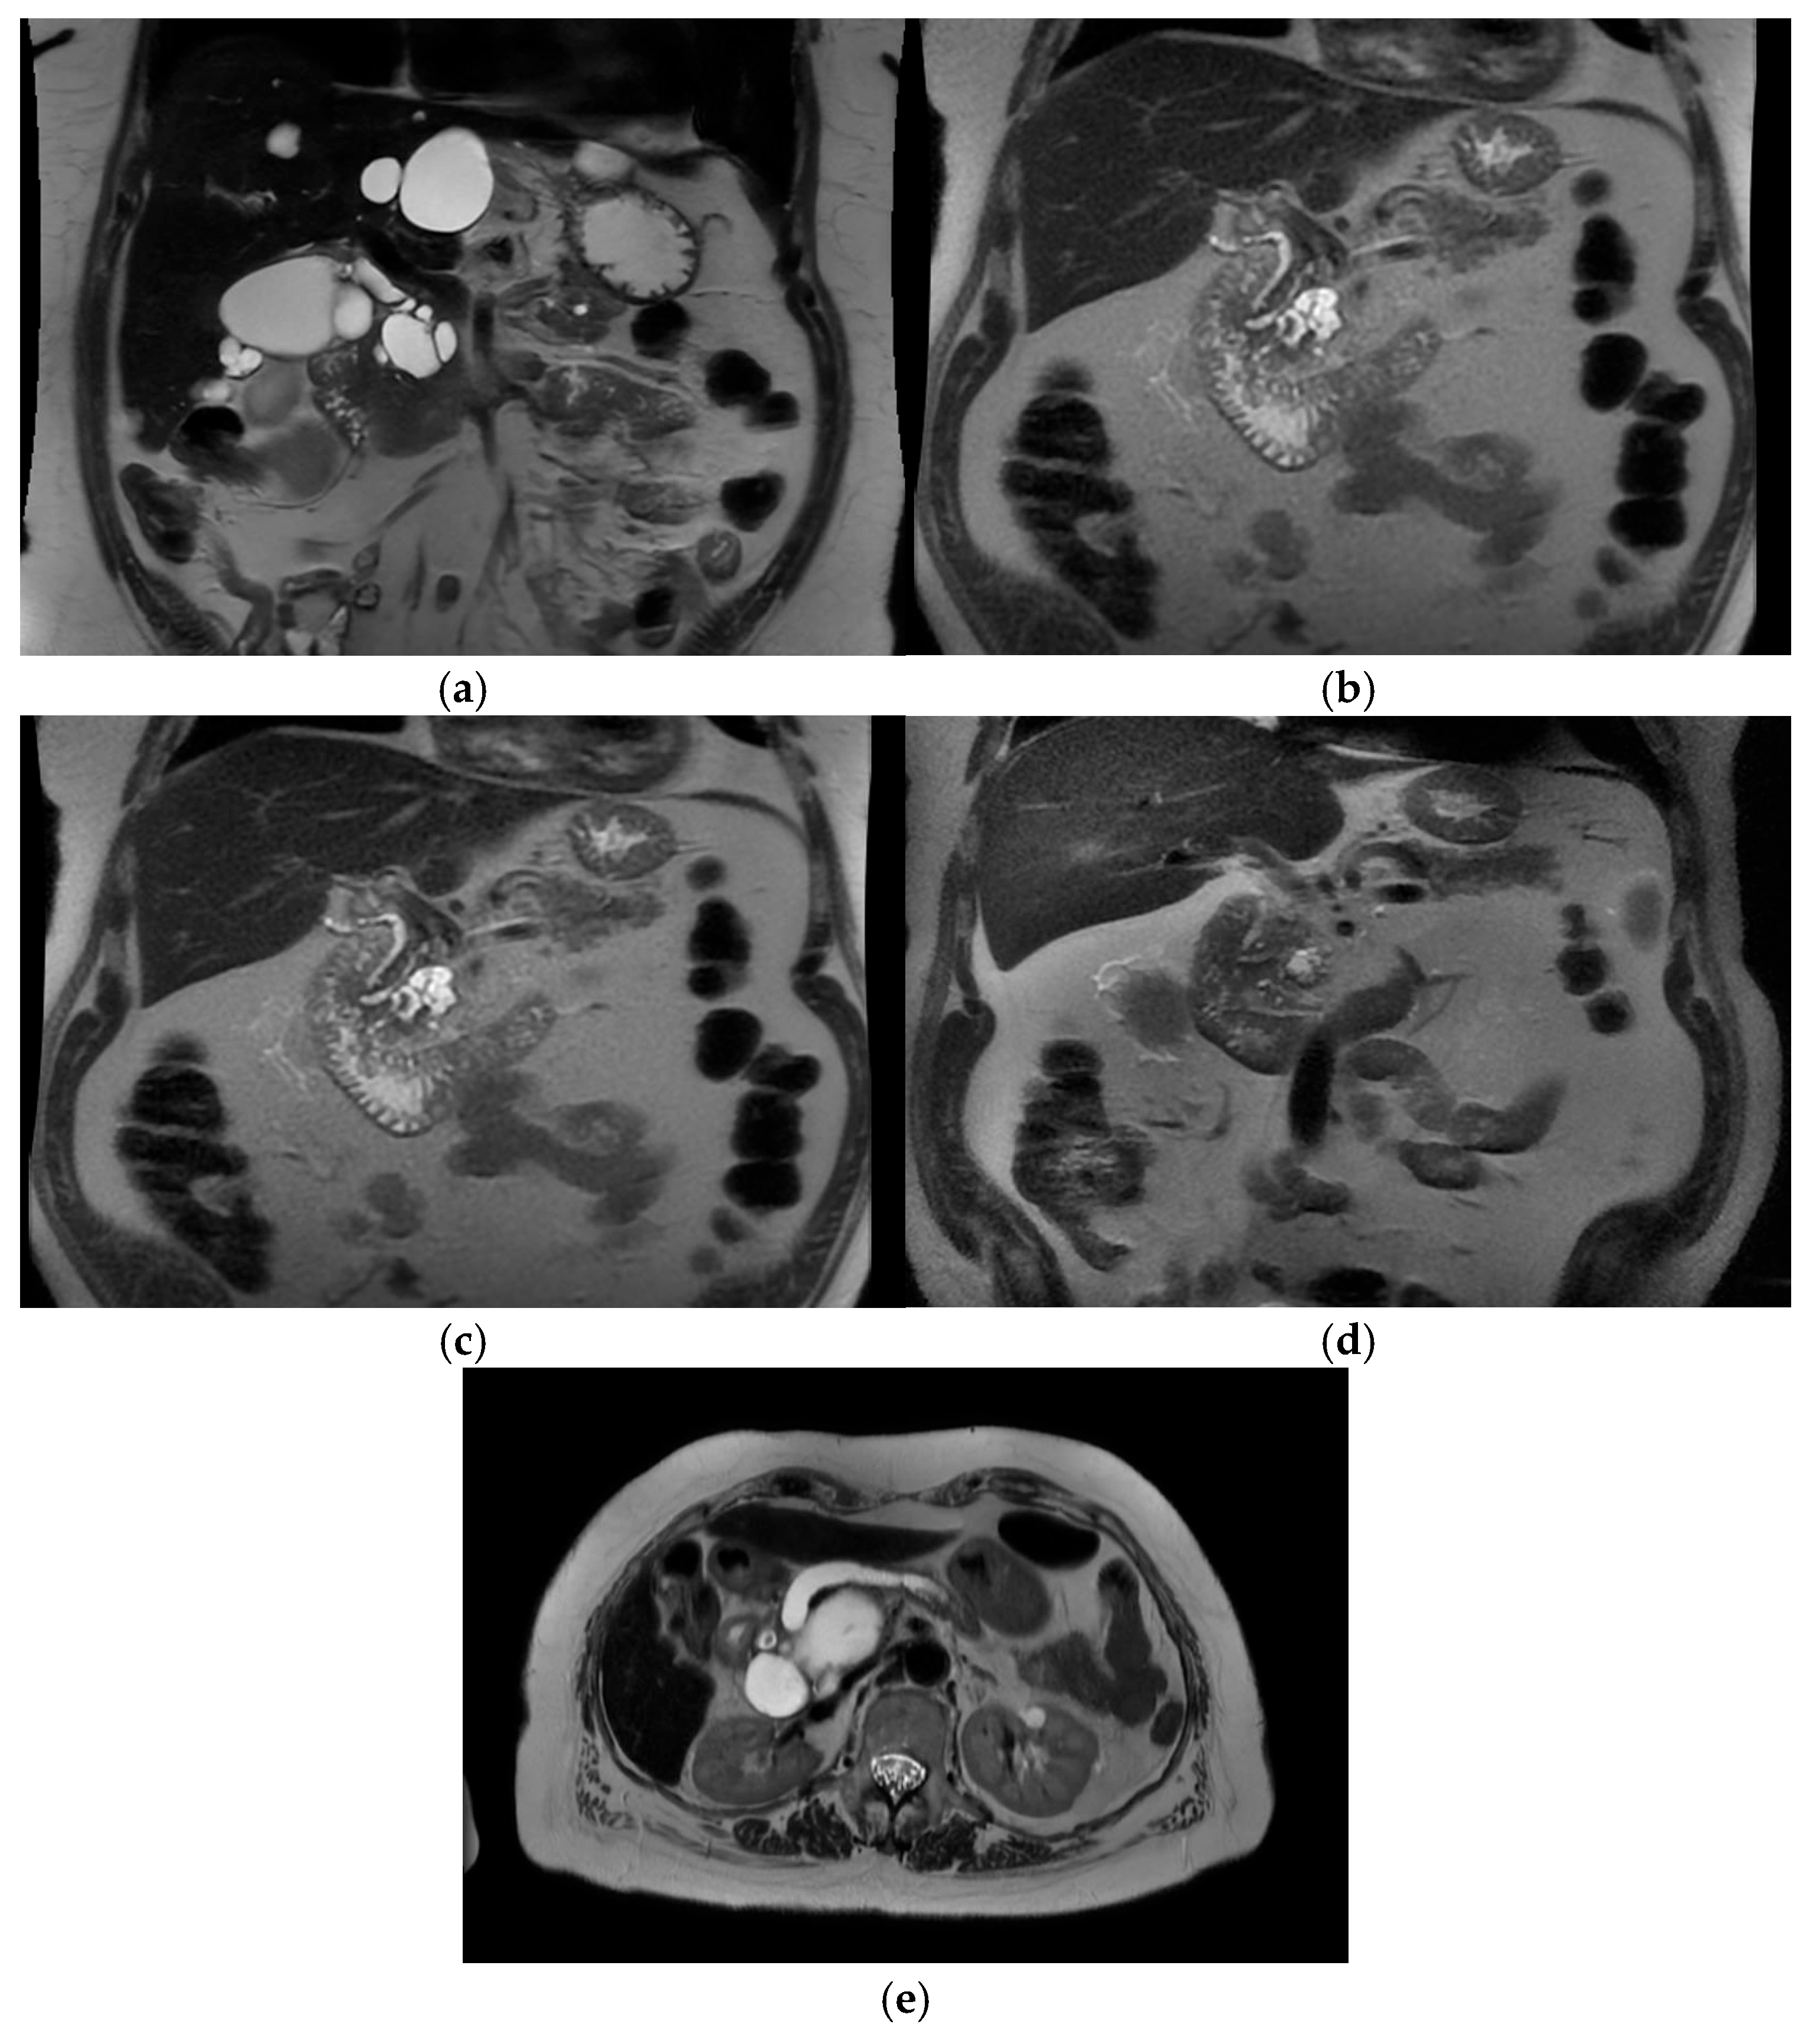

Intra-ductal papillary mucinous neoplasm (IPMN) is a benign condition that has an evolving area of management in the realm of pancreatic surgery. IPMN can be an incidental finding on radiological examinations with CT of the upper abdomen, and may have management with initial surveillance before patients are considered for surgery. See Figure 3a–e.

The characteristic features of IPMN are papillary proliferation of mucin-producing epithelial cells which result in cysts arising from the pancreatic ducts. The cysts can block pancreatic ducts and cause pancreatitis, which is a painful condition that is associated with both IPMN and pancreatic cancer. IPMNs are divided morphologically into 2 groups, depending on whether it is located on the main pancreatic duct or on a branch duct. IPMNs can also be mixed type and show features of both main duct and branch type architecturally. See Figure 4.

Figure 3. Branch duct IPMN and main duct IPMN. (a) Branch duct IPMN. Maximum size 3.2 cm. No other high risk or worrisome features. Incidental liver cysts. Resected—final histology IPMN with low-grade dysplasia. (T2-weighted MRI). (b) Branch duct IPMN >3 cm with thickened septations and nodularity—worrisome features. T2 Weighted MRI. Resected – final histology invasive cancer T3N2. (c) Same patient 1 year prior—approx. 3 cm size, “slightly thickened” septations. (d) Same patient 3 years prior. Smaller cystic lesion. No enhancing component. (e) Main duct IPMN—T2 weighted MRI showing grossly dilated main pancreatic duct.